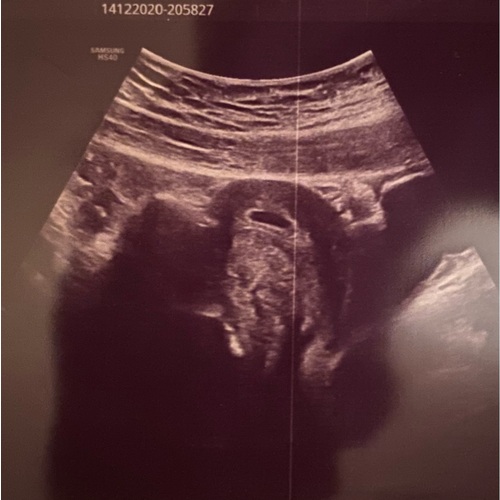

6 weken echo na bloedverlies en stolsels.

Kleine vrucht van 4mm zichtbaar met zelfs een mini hartslag.

Op het scherm kwam ook een vruchtje naar voren.

Het was nu 3.5 centimeter.